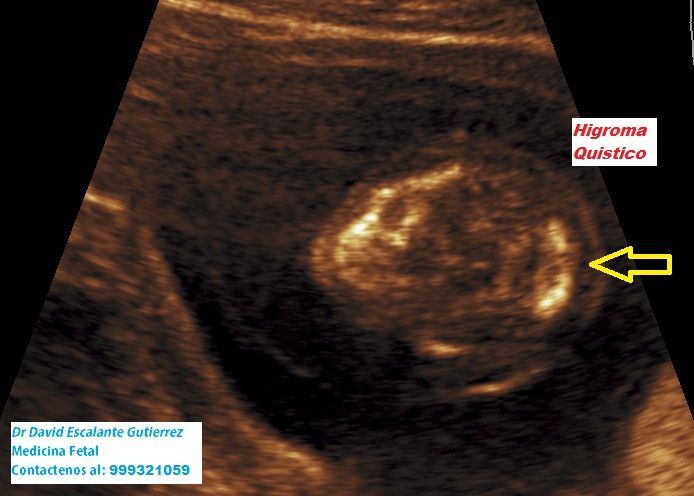

Realizamos las ecografías de viabilidad del embarazo, genética, morfológica, de bienestar fetal, ecocardiografías fetales, así como procedimientos invasivos como biopsia de vellosidades coriales y amniocentesis.